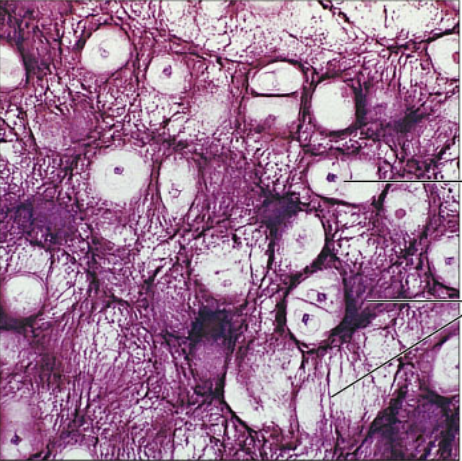

connective tissue proper: hyaline cartilage is found the cartilages of the nose, trachea, and larynx; covers the ends of long bones in joint cavities; and forms most of the embryonic skeleton